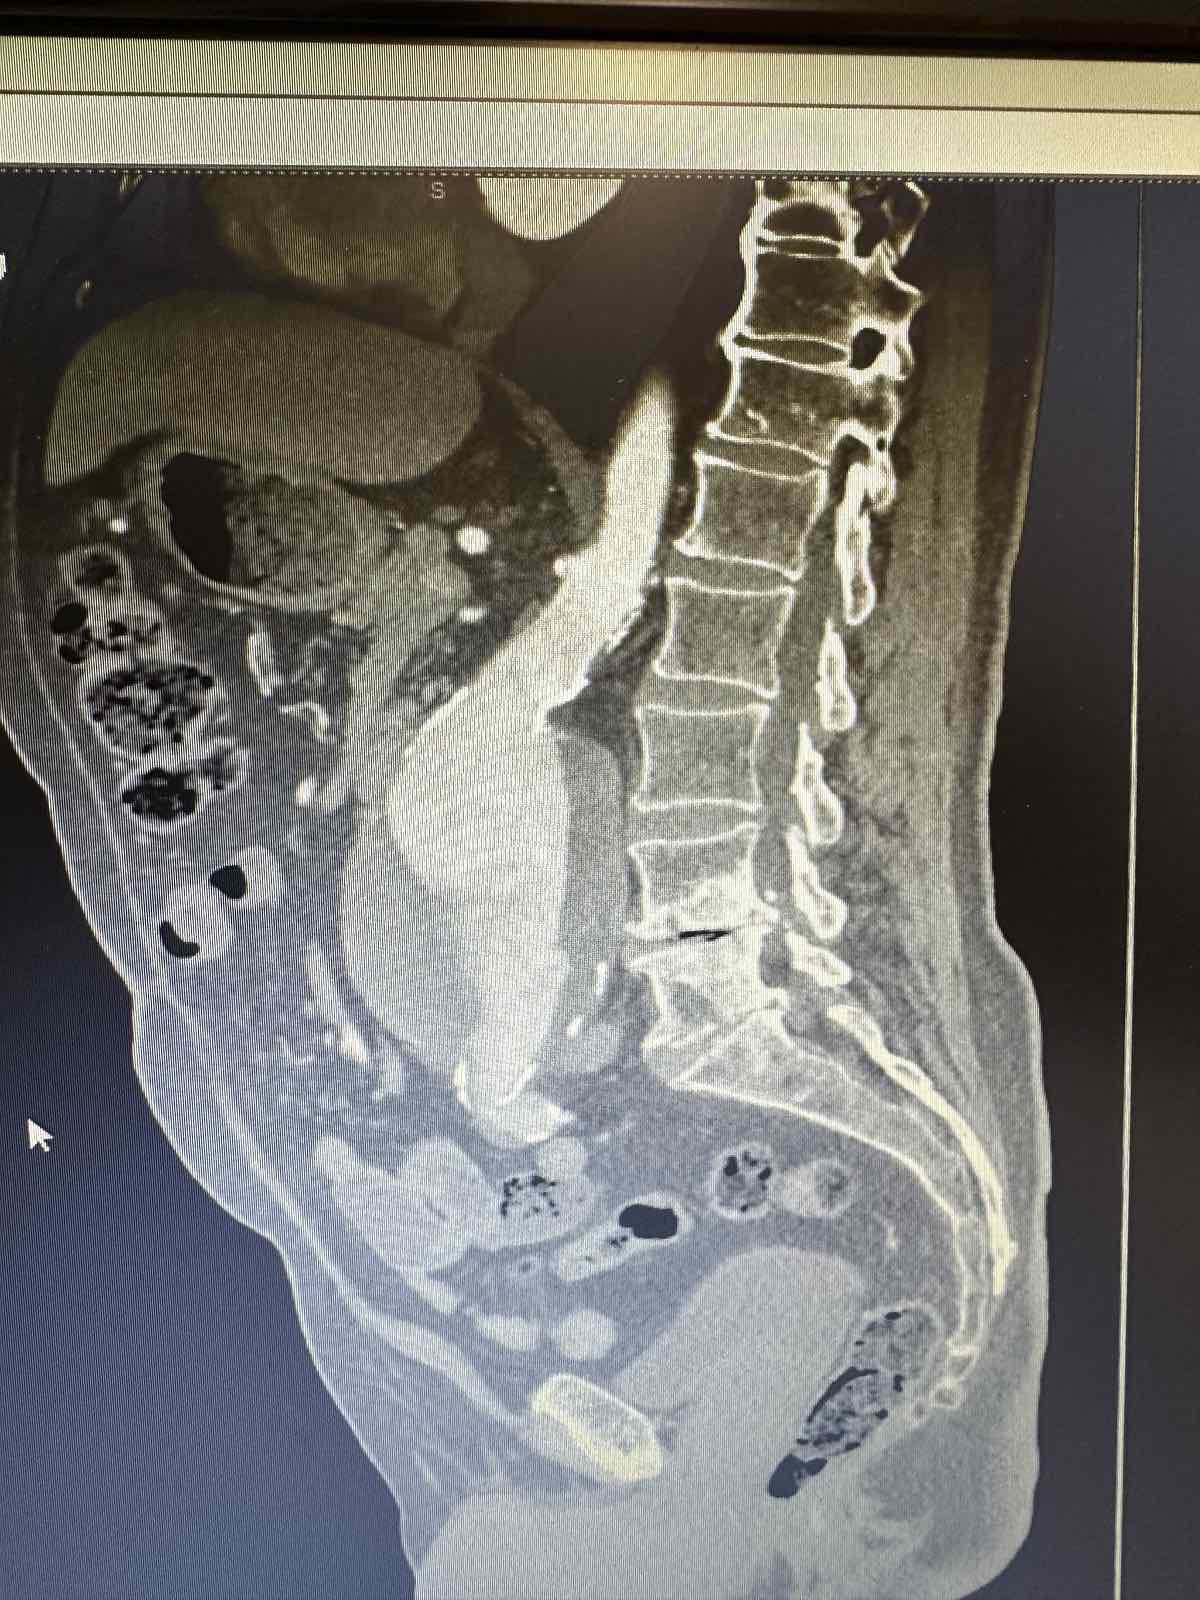

Η διάγνωση του ανευρύσματος κοιλιακής αορτής γίνεται με triplex κοιλιακής αορτής ή αξονική τομογραφία κοιλίας. Κάθε άνθρωπος (στο πλείστο των περιπτώσεων άνδρας) που υπερβαίνει το 60ο έτος της ηλικίας του πρέπει να ελέγχεται με triplex κοιλιακής αορτής (εάν έχει 1ου βαθμού συγγενή με ανεύρυσμα κοιλιακής αορτής η εξέταση πρέπει να γίνει μετά το 50ο έτος). Σε ασθενείς που χρειάζονται αποκατάσταση του ανευρύσματος κοιλιακής αορτής η πιο λεπτομερή προεγχειρητική εξέταση είναι η αξονική αγγειογραφία κοιλιακής αορτής και λαγονίων. Σε ασθενείς που δεν μπορούν να υποβληθούν σε αξονική αγγειογραφία διενεργείται μαγνητική αγγειογραφία κοιλιακής αορτής και λαγονίων.